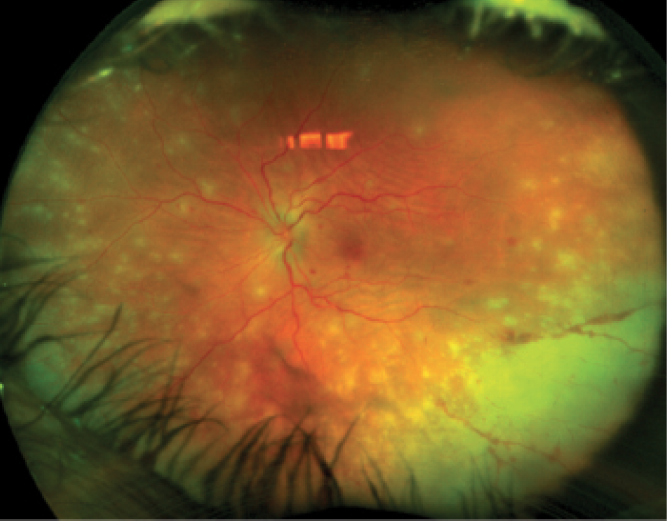

Figure 1. Widefield fundus photo of the left eye of a 56-year-old woman with a 3-week history of blurriness and pain. Polymerase chain reaction of aqueous humor revealed the presence of varicella zoster virus particles.

Color photos are helpful in documenting anterior segment, retinal, and choroidal lesions. They can also be helpful in monitoring progression of the disease, size of the lesions, appearance of new lesions, and response to treatment (Figure 1). As treatment progresses, color photos can be used to document the progress of lesion regression. In rare cases of diffuse unilateral subacute neuroretinitis, motile larvae are often found more easily on color fundus photography with good sweeps, leading to a definitive diagnosis (Figure 2).6 We tend to prefer regular color photos with sweeps over widefield images that are in false color, as the larvae are seen more easily.